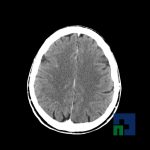

Examinare de rutină cerebrală, nativ și cu substanță de contrast (SDC) pentru diagnosticul:

- Accidentelor vasculare cerebrale ischemice sau hemoragice

- Evaluarea deplasării liniei mediane

- Evaluarea cisternelor perimezencefalice

- Diagnosticul edemului cerebral, a contuziei cerebrale, a leziunilor axonale difuze edematoase/hemoragice, a dilacerării cerebrale, a hematomului intraparenchimatos posttraumatic, a hematoamelor subdurale/extradurale (acute, subacute, cronice), a hemoragiei intraventriculare, a hemoragiei subarahnoidiene